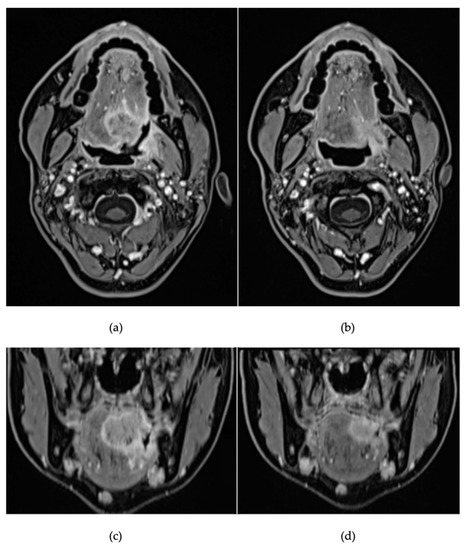

2. Detailed Case Description